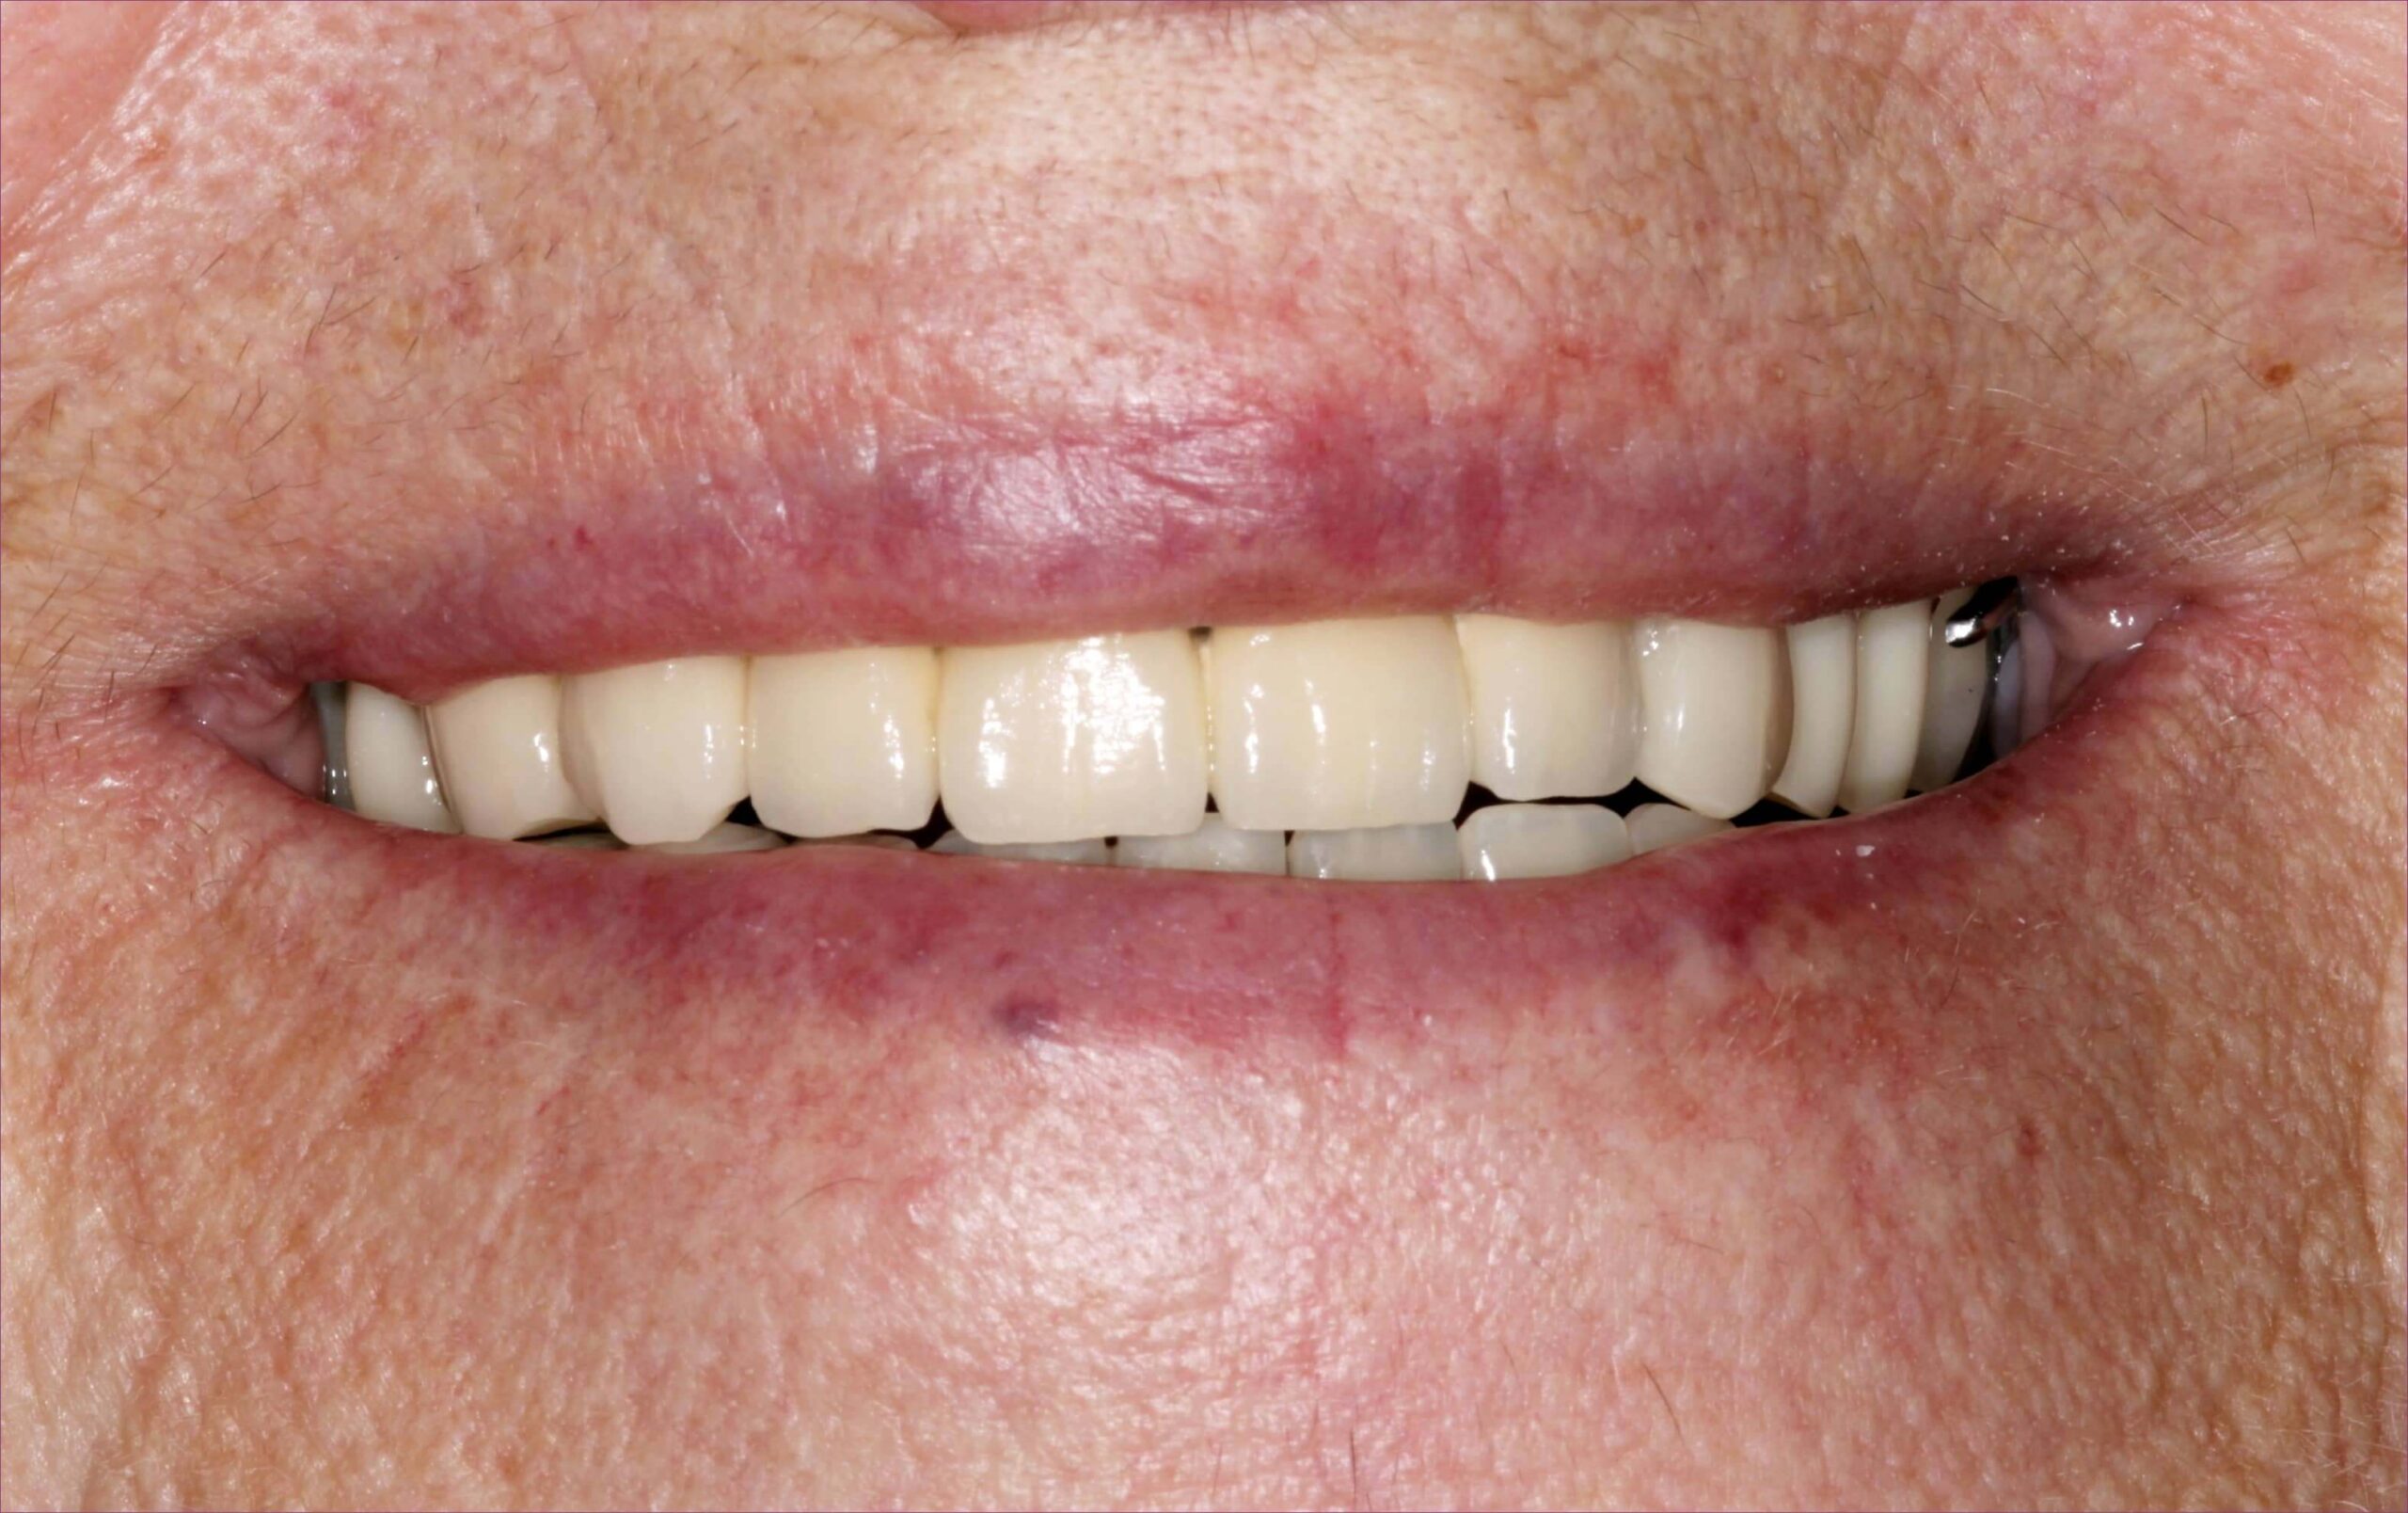

Végül a kezeléssorozat végén átadásra kerültek a fogpótlások. Az összkép a megérkezési állapottal összehasonlítva drámai változásokat mutat.

Nem csoda, hogy ilyen elégedett a mosolya, hiszen a megújult fogsora mellé „grátiszként” még a krónikus fájdalmai is elmúltak…